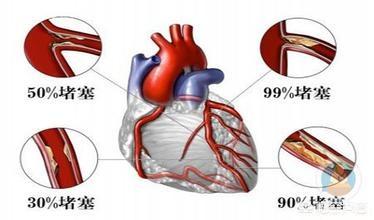

47歳の朱さんは、1年前に心電図で70%の狭窄を指摘され、心配していた。

医師の指導の下、1年間服薬を守り、健康的な生活を続けた結果、最近の経過観察の画像診断では、その血管の狭窄は改善し、現在は50%にとどまっている。

頸動脈プラークが50%未満でLDLが高くない場合は、投薬しなくても一時的に観察することができる。頸動脈クラス狭窄が50%以上、またはプラークが柔らかい場合は、プラークをコントロールするためにスタチン投薬が必要である。心血管プラークも悪化を防ぐためにスタチンの服用が必要である。また、糖尿病、高血圧、高脂血症を積極的にコントロールする必要があり、LDLの目標値は理想的には2.6未満、あるいは1.8未満まで下げるとより安全である。

運動やトレーニングの強化に加え、血管プラークの問題がある人には、脂質プロファイルに応じた薬物療法で脂質の目標値をコントロールする必要がある。まだ心血管疾患を発症していないが、心血管疾患のリスクが高い友人に対しては、LDLコレステロールを2.6mmol/L未満にすることを脂質コントロールの目標とし、心血管疾患を発症した患者に対しては、この値を1.8mmol/L未満にコントロールする。脂質コントロールの主薬はやはり先に述べたスタチン系薬剤であり、スタチン耐容性のある患者には、エゼチミブやプロブコールなど他の脂質低下薬の併用を考慮し、複合的な脂質コントロールを行う。

アテローム性動脈硬化症は50歳以上の80%にみられ、頸動脈プラークの発生率は加齢とともに増加する。 少数の高齢者では、プラークは狭窄に至り、血行動態の変化や閉塞を引き起こすことさえある。

プラーク発生率は50〜59歳の患者に比べて60歳以上の患者で有意に増加したが、60歳以上のプラーク発生率の差は小さく、プラーク発生率は中高年に比べて高齢者で有意に増加することが示された。

重要なのは特に冠動脈、頭頸部動脈に50%の動脈狭窄や不安定なプラーク形成がある動脈プラーク患者には、アスピリンと併用してスタチン療法を行うべきである。プラークを狭窄・安定化させるスタチンと、破裂した内皮での血栓症を予防するアスピリンの併用は、心血管イベントのリスクを有意に低下させるため、動脈プラークの治療と心血管・脳血管イベントの予防のための古典的な組み合わせであり、礎となる薬剤である。